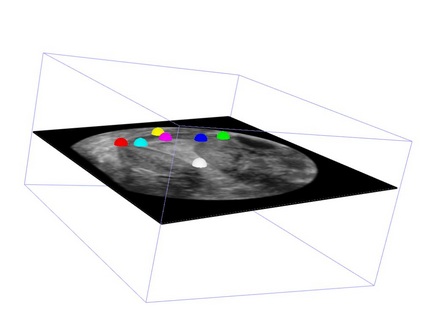

Standard plane (SP) localization is essential in routine clinical ultrasound (US) diagnosis. Compared to 2D US, 3D US can acquire multiple view planes in one scan and provide complete anatomy with the addition of coronal plane. However, manually navigating SPs in 3D US is laborious and biased due to the orientation variability and huge search space. In this study, we introduce a novel reinforcement learning (RL) framework for automatic SP localization in 3D US. Our contribution is three-fold. First, we formulate SP localization in 3D US as a tangent-point-based problem in RL to restructure the action space and significantly reduce the search space. Second, we design an auxiliary task learning strategy to enhance the model's ability to recognize subtle differences crossing Non-SPs and SPs in plane search. Finally, we propose a spatial-anatomical reward to effectively guide learning trajectories by exploiting spatial and anatomical information simultaneously. We explore the efficacy of our approach on localizing four SPs on uterus and fetal brain datasets. The experiments indicate that our approach achieves a high localization accuracy as well as robust performance.